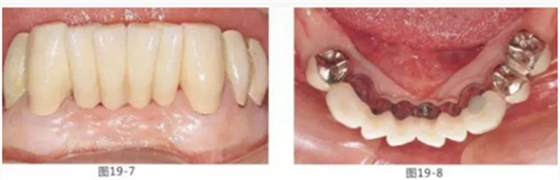

圖19-7 佩戴最終修復(fù)5年后的唇頰側(cè)面照。

圖19-8 同時(shí)期下側(cè)咬合面照。